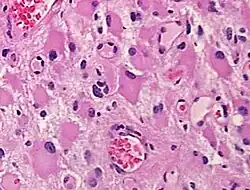

Histopathology of a gemistocytic astrocytoma. Neoplastic gemistocytes are angular shaped with abundant, glassy, eosinophilic cytoplasm and eccentric nuclei with distinct nucleoli.

When present in anoxic-ischemic brains, gemistocytes are regularly encountered in glial neoplasms, also known as glioma, which is a type of tumor that occurs in the brain and spinal cord. Usually, gliomas begin in the glial cells that surround the nerve cells to help them function. Many gliomas exhibit cells that do not exist in normal brain tissue and are not seen in glial differentiation.[1] Of these gliomas are astrocytomas, which is a type of cancer that occurs in the brain or spinal cord. The main role of astrocytes is to maintain brain homeostasis and neuronal metabolism. When the astrocytes become activated, they begin to respond to damage.[3] Astrocyte activation, known as astrogliosis, responds to neurological trauma, infections, degradations, epilepsy, and tumorigenesis. Each neurological insult plays a major role in astrocyte activation and response to that specific damage. In some astrocytomas, the number of gemistocytes is extremely overwhelming, terming it a “gemistocytic astrocytoma.” Not only are gemistocytic cells present in astrocytomas, but they are also found in various glial tumor cells; for example, oligodendrogliomas, mixed oligoastrocytomas, glioblastomas, and pleomorphic xanthoastrocytomas. Gemistocytes are known to have a large cytoplasmic mass, long, branching processes, and increased cytoplasmic filaments.[1] The cytoplasm of gemistocytes stains positive for glial fibrillary acidic protein, GFAP. While the intermediate filaments in gemistocytes are diffused throughout the cytoplasm, which indicates cellular disintegration. Within these different tumor types, the term “mini-germistocytes” is used for smaller gemistocytes, that are usually found in oligodendroglial tumors. Mini-germistocytes are found to have a very ordered arrangement of filaments throughout the cytoplasm, but may also transform into the end-state morphology of the larger gemsitocytic cells. Studies have suggested that both classic gemistocytes and mini-gemistocytes show similar genetic variation to non-gemistocytic tumor cells.[4] Mini-germistocytes, usually found in oligodendroglial tumor cells, express gliofibrillary oligodendrocytes, or GFOCs, which are capable of transforming the mini-gemistoctyes into larger gemistocytes.